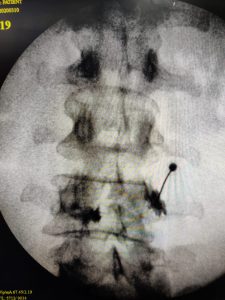

Selective nerve root block or SNRB, is a technique in which the specific nerve is blocked under computer control called fluoroscopy. The nerve location is confirmed with a dye and problem is relieved with an injection.

Facet joint blocks are targeted injections that are administered under computer guidance into the facet joint to lubricate the joint and get them to move again.

Injections given into the sacro iliac joints under fluoroscopy is an important modality in treating chronic ailments not responding to medicines and physical therapy.